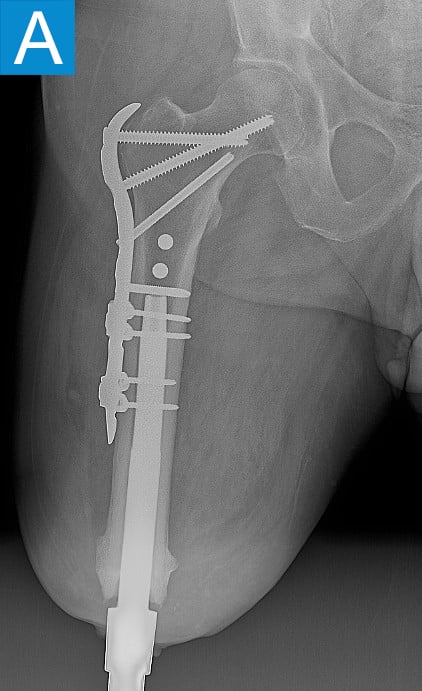

He started progressively loading the implant at 2 weeks and received his full prosthetic leg with simple hinged knee at 6 weeks. At 3 months he no longer used assist devices and at 3.5 months his prosthesis was changed to a microprocessor-controlled knee. Shortly after receiving the new knee, he stumbled stepping over a ledge and fell, sustaining a subtrochanteric proximal femur fracture (Figure 2b). The fracture extended to the tip of the implant, which remained stable in the bone. He underwent open reduction and internal fixation of the femur fracture with a proximal locking plate (Figure 2c). He did not wear the prosthetic leg for 10 weeks, when he began gradually loading the femur. He resumed full weightbearing without assistive devices about 6 weeks later.

Figure 2. Postoperative X-rays shows (A) a femoral osseointegration implant; (B) a subtrochanteric proximal fracture; (C) the femur fracture repaired by open reduction and internal fixation with a proximal locking plate.